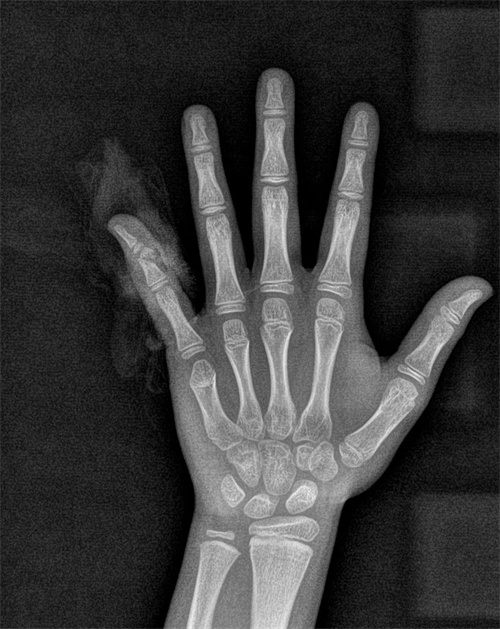

佳佳手术前x线检查结果

8岁的佳佳是个活动好动的小男孩,这个暑假在自家楼下玩滑板车时,因速度未控制好而失去平衡摔倒,左手小指流血不止,被送到湖南省人民医院骨科六病区(手足显微外科)就诊,经过仔细检查,发现孩子的小指已经差不多完全断离,经过急诊手术接受了断指再植,将离断的血管和神经接上,才没有影响手指的功能。